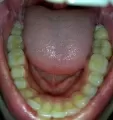

Всегда были ровные зубы, пока не вырос внизу зуб мудрости, который искривил зубы, т.к. мои растут плотно друг к другу. Мне 39, думаю, еще один уже не прорежется.

Что делать в такой ситуации, удалять зуб, потом ставить брекеты? Только на нижнюю челюсть? Можно ли исправить ситуацию без брекетов? Верхние зубы трогать не буду, они идеально ровные.